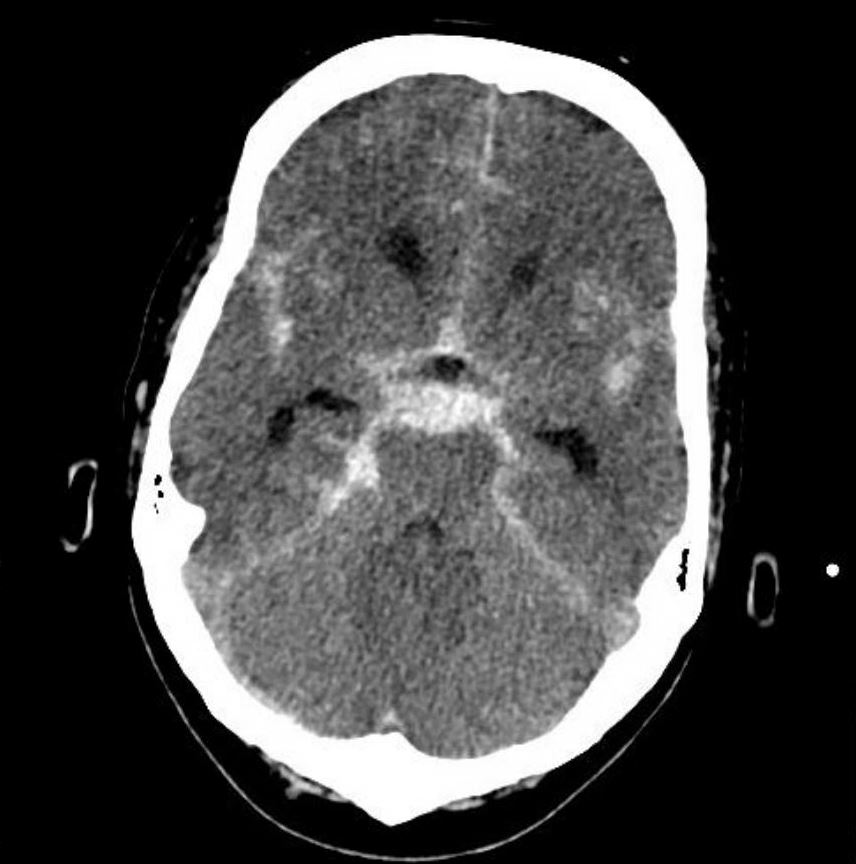

Hi allerseits, meine Mutter ist nun seit etwa einem Jahr in der Reha. Sie hatte im Juli vergangenen Jahres eine Kleinhirnblutung. Definition: Unter einer Hirnblutung sind Einblutungen in das Gehirn selbst oder seine Hüllstrukturen zu verstehen, die zu erhöhtem Hirndruck und .

Anzeichen für eine subdurale Hirnblutung sind zum Beispiel: Bewusstseinsstörungen, unterschiedliche Pupillengröße bei Lichteinfall und Streckkrämpfe . Ich wollte mal fragen, ob jemand von Euch schon mal eine Hirnblutung erlitten hat, wie es demjenigen heute geht und wie er seine Energie . Bei einem Schlaganfall durch Hirnblutung (hämorrhagischer Hirninfarkt) platzt ein Blutgefäß im Gehirn. Wichtig ist, früh auf die Symptome einer Hirnblutung zu reagieren und nach bildgebender Darstellung einer Hirnblutung rasch eine Therapie .

Jeder zweite Patient stirbt an Blutungen, die durch eine ausgebeulte Ader im Gehirn ausgelöst werden. Das wichtigste bei der diagnose hirnblutung ist die zeit. Bei einer Hirnblutung hängt die Behandlung davon ab, an welcher Stelle die Blutung entstanden ist und welche Symptome auftreten. Gestern erhielten wir, mein Freund und ich, den Anruf, dass seine beste Freundin mit Hirnblutung ins Krankenhaus gekommen ist. Bei einer Hirnblutung treten Einblutungen in das Gehirn oder in seine Hüllstrukturen auf.